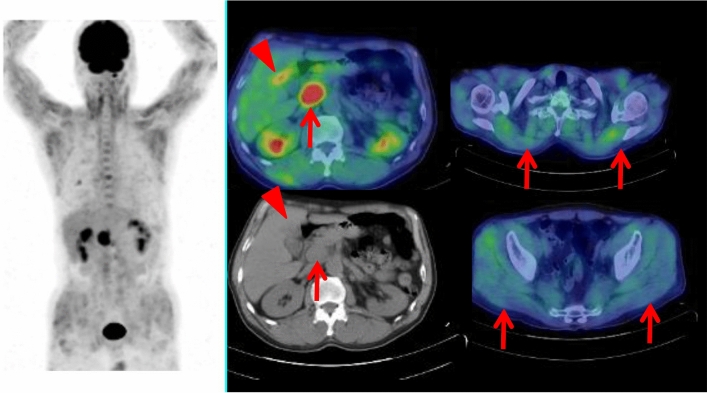

Fig. 3.

A 71-year-old female with transcriptional intermediary factor 1-positive dermatomyositis was treated with corticosteroid. This patient had a history of thyroidectomy for thyroid cancer 7 years ago. Whole-body FDG PET maximum projection image showed increased FDG uptake in systemic muscles. Cross-sectional FDG PET/CT images showed focal FDG uptake (SUVmax 5.7) in the descending colon, which was diagnosed as colon cancer by endoscopic biopsy (arrows)

Fig. 4.

A dusky red rash developed systemically in the skin with itch in a 63-year-old male. Whole-body FDG PET maximum projection image showed heterogeneously increased FDG uptake in the systemic muscles. Cross-sectional FDG PET/CT images showed FDG-avid (SUVmax 3.1) gall-bladder cancer (arrow head) and metastatic lymph node near the root of the superior mesenteric artery (arrow), with heterogeneous but almost symmetrically increased FDG uptake in the muscle tissues (arrows)